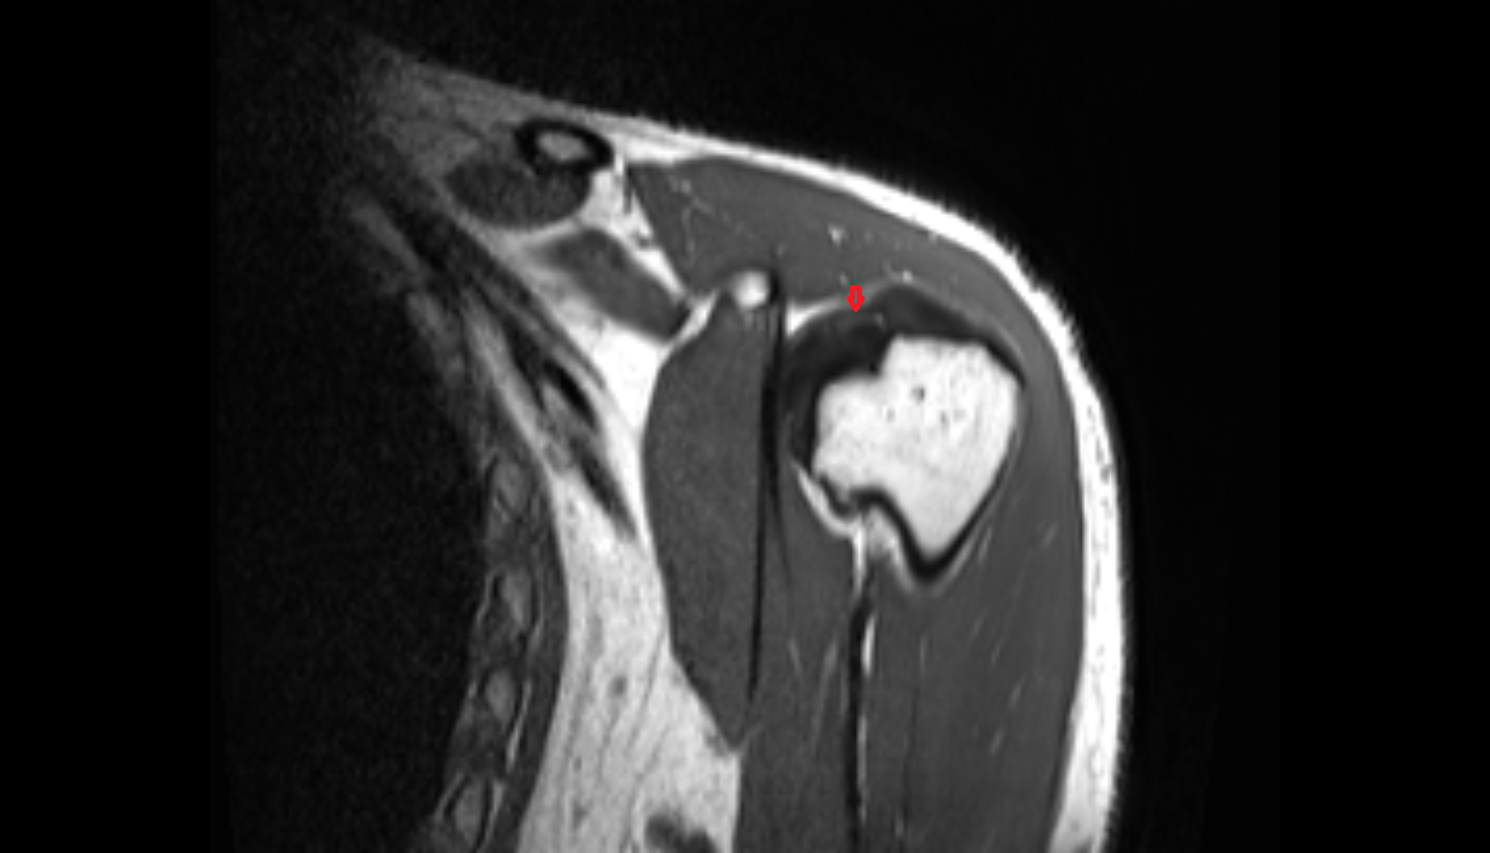

- Supraspinatus tendon

- Subacromial space

- Shoulder joint (glenohumeral joint)